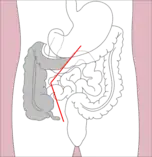

- Right hemicolectomy and left hemicolectomy refer to the resection of the ascending colon (right) and the descending colon (left), respectively. When part of the transverse colon is also resected, it may be referred to as an extended hemicolectomy.[5]

Right extended hemicolectomy Left hemicolectomy

Left hemicolectomy Extended left hemicolectomy